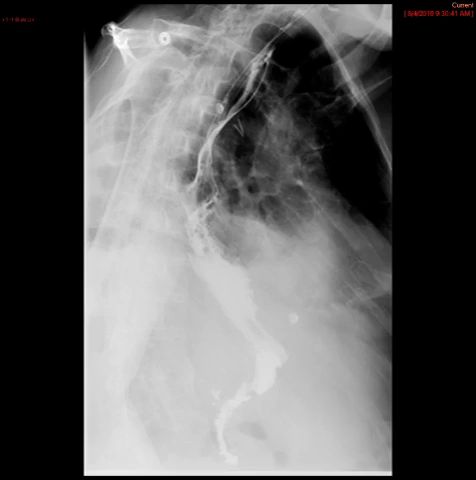

- The technologist will obtain a scout radiograph(s) to include the chest and upper abdomen to determine the location of the surgical chain sutures or surgical staples

(key image 1).